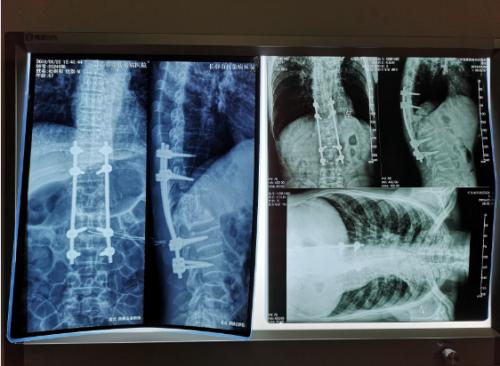

在长春市传染病医院骨科·普外科的走廊里,王大爷和老伴握着医生的手万分感激。光看他的脸色与精神,很难想象他曾经还是一位有下肢瘫痪的骨结核患者,结核杆菌在他的胸椎上肆虐大半年之久,侵蚀了多个椎体。但这一切已成为过去,在骨科·普外科全体医护人员的努力下,已经可以像正常人一样行走了。所幸的是,长春市传染病医院成功为其实施了脊柱畸形矫正、椎体结核侧前方减压灶清除椎间植骨术,为王大爷解除了疾痛,长春市传染病医院的手术是省内此类手术的领先水平。

经过检查,罗坚主任凭着丰富的临床经验初步认为王大爷患的是胸椎结核伴脊髓压迫症,那么是什么原因造成的?通过脊柱磁共振检查,罗主任发现王大爷患胸椎脊髓压迫的元凶正是“骨结核”。王大爷胸椎骨7-11节被结核杆菌严重侵蚀,在重体力活后,胸椎脊髓神经受到压迫,最终导致下肢瘫痪。同时患者双肺结核伴左上叶不张,左侧胸腔大量积液。如果等待双肺结核治愈,需时日很长,脊髓的受压如果不能及时解除,导致脊髓变性,那么瘫痪就难以恢复了,在积极治疗肺结核胸腔积液引流,罗坚主任为王大爷尽快安排实施手术。

手术过程中,病人腰大肌脓肿巨大,病椎破坏重游离死骨多,结核物质使脊髓严重受压,既要侧前方减压清除病灶,又要完成后凸畸形的矫正,再由于王大爷年龄较大、体质差,风险高,对技术与手术期管理都是很大的挑战。

罗坚、陈松峰和任重三位医师组成的团队实施手术。罗坚主任凭借其多年外科生涯中大量胸椎结核手术所积累的丰富经验,在脊柱侧前方减压,病灶清除、植骨和后凸畸形矫正胸膜外操作。手术按计划顺利完成,而辗转数家医院的“求医记”终于告一段落,在外等候的家人听到手术成功的消息后喜极而泣。